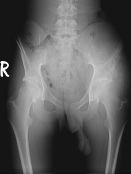

Kıkırdak hücresi üreten kötü huylu bir tümördür. En sık 30-60 yaş arasında görülür. Sıklıkla femurun (uyluk kemiği) her iki ucunda, humerusun (kol kemiği) üst ucunda, pelvis (leğen kemiği), kaburga, omurga ve kafa kemiklerinde görülebilir. Kondrosarkomlar primer ve sekonder olmak üzere iki gruba ayrılır. Elde nadir görülmesine karşın malign el tümörleri içerisinde üst sıradadır.

1. Klasik Medüller Kondrosarkom

Sıklıkla pelvis (leğen kemiği), femurun (uyluk kemiği) ve humerusun (kol kemiğinin) üst ucunu tutar. Kondrosarkomların %80’nini oluşturur. 30 yaş üzerinde sık görülür. Grade I kondrosarkomlarda lezyon içerisine girilerek geniş küretaj yapılır. Grade II ve üzeri lezyonlarda lezyon için cerrahi girişimlerde lokal nüks riski çok yüksektir. Bu tip kondrosarkomlarda mutlaka geniş sınırlar ile rezeksiyon yapılmalıdır. Histolojik derece çok yüksek ise kemoterapi eklenebilir.